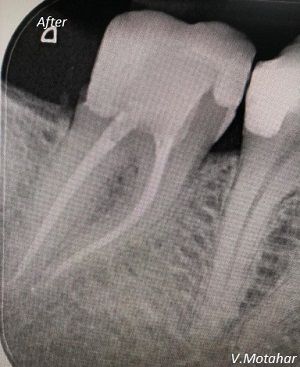

Root Canal treatment on Lower molar tooth immediate after the Root Filling!

before

after

Root canal treatment on three rooted tooth! which had 4 canals!